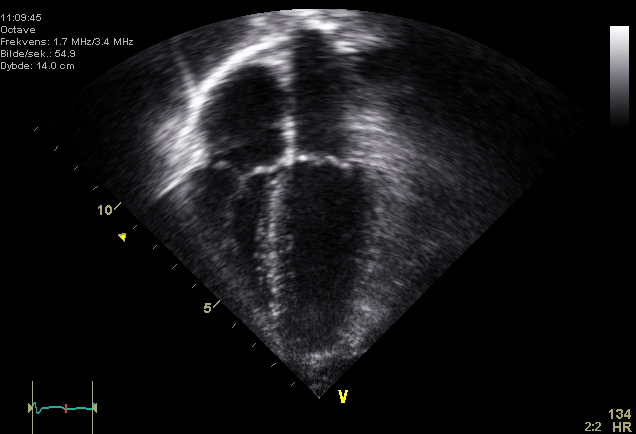

2D Echo

A Two-Dimensional Echocardiography (2D Echocardiogram) is an ultrasound that can capture high-quality scans of the heart as well as its vessels. It can also monitor your heart’s blood flow in order to check if your blood vessels are properly functioning.

A transducer is used in this test to send and receive signals. A doctor will hold the hand-held transducer to your chest. Sound waves emanate from the transducer and are directed to the heart. These sound waves bounce off of the walls of your heart and valves back to the transducer. The device then calculates the signals it has received back to produce pictures of your heart. The images will appear black and white on a screen, at which point a select portion of it will be recorded on videotape and on a specialized paper.

Physicians will measure the size of each part of your heart to study its motion and appearance for any abnormalities. Another test that you should expect in a Basic Cardiac Package is a Treadmill Stress Test.